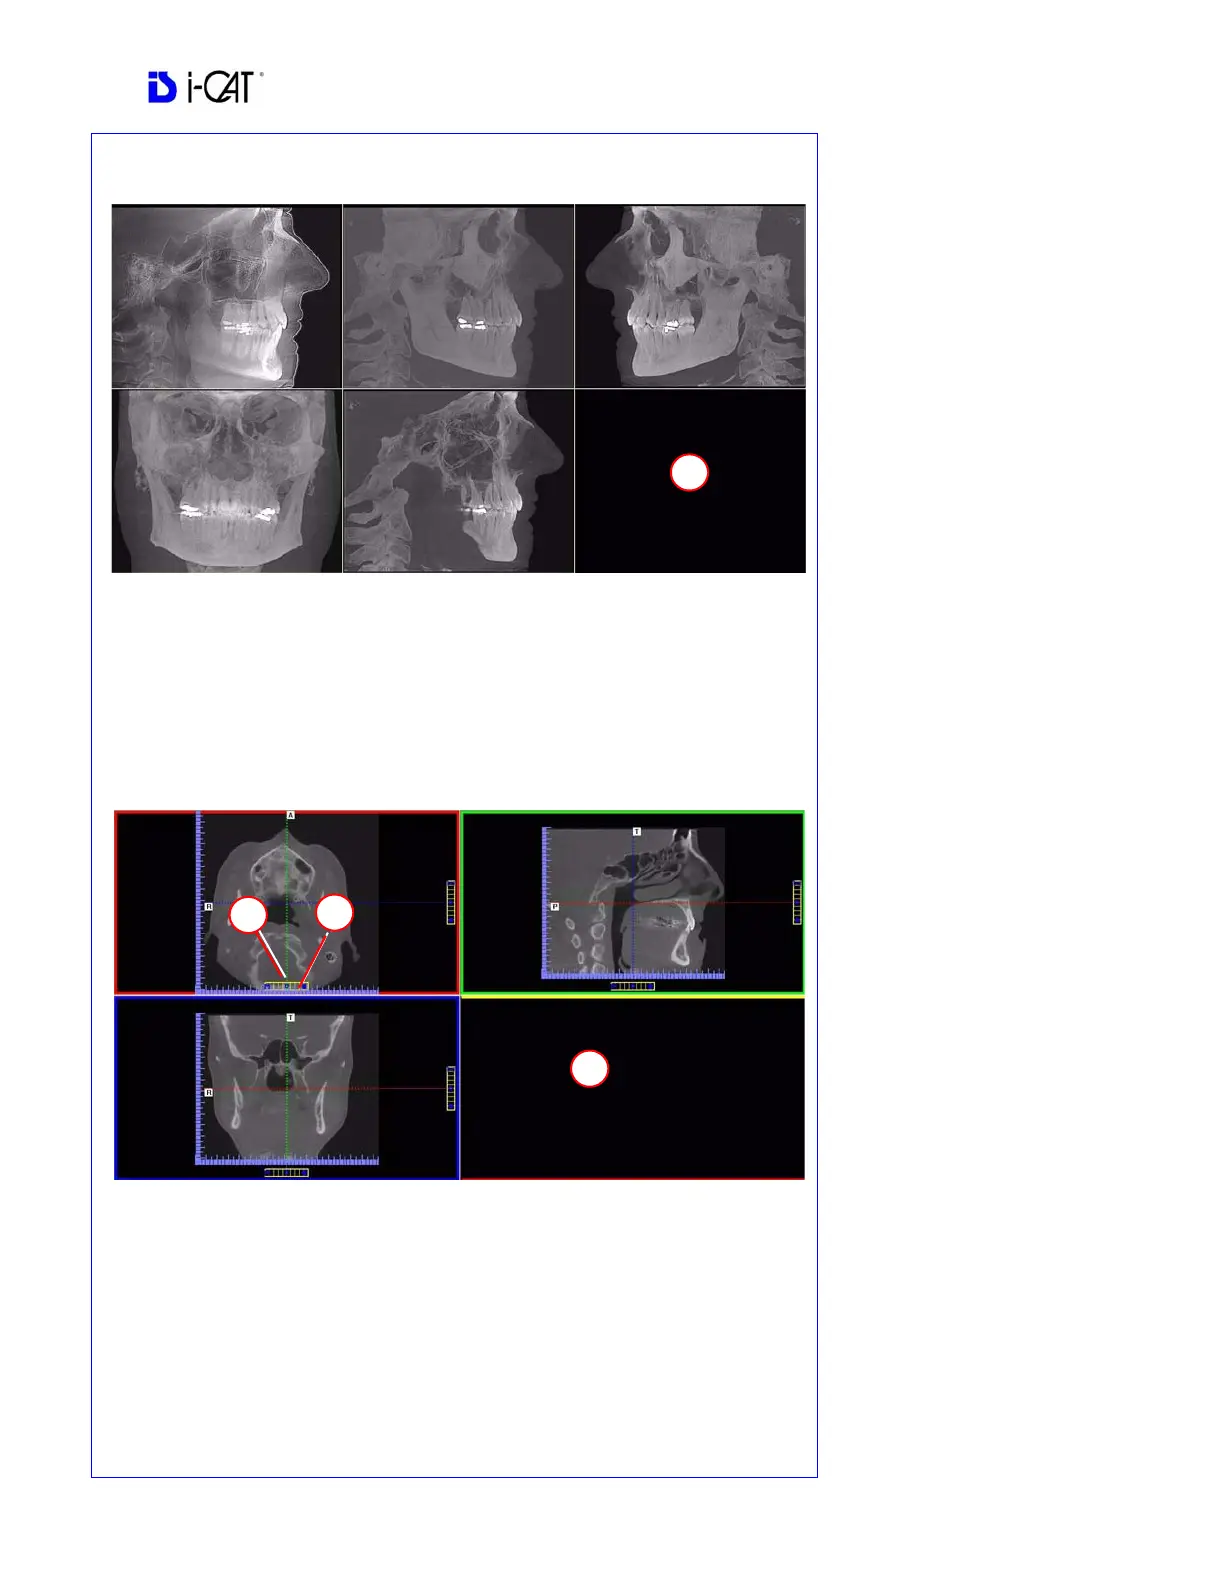

Ceph Screen

1. Right click blank screen and select Tag Airways. This generates a 3D view of the

airways for the patient in the blank view. In addition, the tagged airway data is

displayed in the view at the bottom center of the Ceph screen.

MPR Screen

1. Drag center tools from any view to move slice location. The views are colored coded

to correlate which view will adjust.

2. Drag tool to the right for horizontal and bottom for vertical bars to adjust slice

thickness of the corresponding color coded view.

3. Right click any of the 3 views and select Irregular, Line, or Explore for additional

cut planes to be displayed in the blank area.

REMINDER

Ceph Screen is acquired by double

clicking Sagittal View from Preview

window or selecting it from the

Screen menu.

DISPLAYED VIEWS

The Ceph Screen displays the

Lateral Cephs in Radiographic and

MIP mode as well as a Coronal

View and a Mid Sagittal Slice

(15mm thick).

MPR Screen is acquired by double

clicking Coronal View from

Preview window or selecting it from

the Screen menu.

The MPR Screen allows scrolling

through the Axial, Sagittal, and

Coronal Slices. Mouse scroll wheel

is active to scroll through slices.

POP UP MENUS

Right click to display the Pop Up

menu to select:

Irregular

Line

HU Statistics

Distance

Explore

Explore Speed

Set Filters

Save as JPEG

Open Output Folder

Reset Volume Rotation